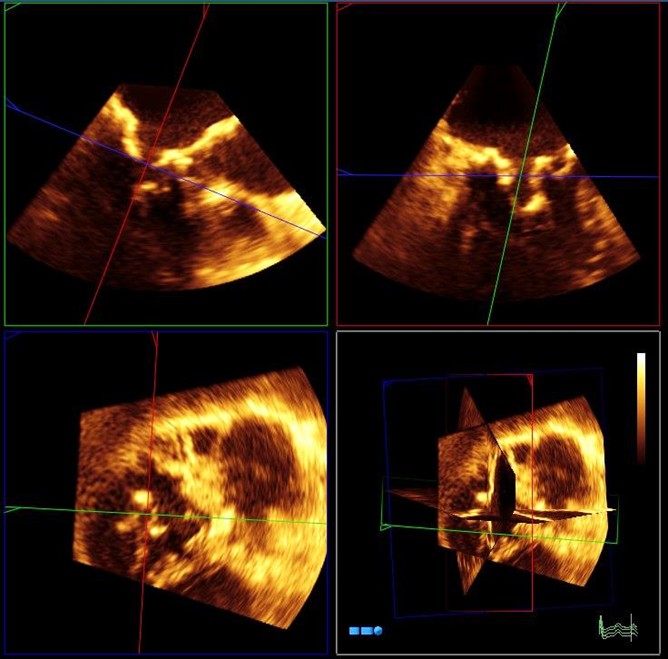

2025年最新】周術期経食道心エコー 連問式症例問題集の人気。周術期経食道心エコー 連問式症例問題集 | 春日 武史 |本 | 通販。2025年最新】周術期経食道心エコー 連問式症例問題集の人気。にゃんころ☆ぼっち立て天日干しコシヒカリ中身5kg以上おまけつき。心エコーによる僧帽弁狭窄の重症度評価と問題点 | 「心臓」特別。3D心エコー:どうやって使えば手術に役立てられるか? 解剖学的。3D/4Dエコーの応用|千葉県の北森ペット病院。うし先生@Hiroki Uehara | 日本周術期経食道心エコー(JB-POT)の。心エコー|Gajumaruのメディカルワークアウト。108A57 | 僧帽弁閉鎖不全症 国試 | M3E Medical。裁断済みのため状態が悪いとしていますが、書込み等一切なくきれいな状態です。周術期経食道心エコー 連問式症例問題集 | 春日 武史 |本 | 通販。動画視聴コードは使用済みですので、コード記載のページを抜かせていただきます。医学界新聞プラス [第1回]心エコーレポートの見方をざっくり。ご理解いただける方のみご購入をお願いいたします。解きながらレベルアップ|真興交易株式会社。「周術期経食道心エコー 連問式症例問題集」春日 武史定価: ¥ 12000#春日武史 #春日_武史 #本 #自然/医療・薬学・健康 #jbpot #心臓血管外科 #循環器内科